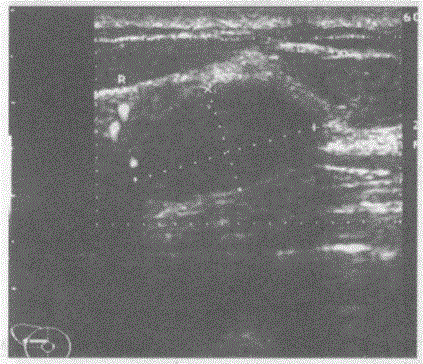

问题 临床资料:女,21岁,自述洗澡时无意中发现右乳腺肿物。 临床物理检查:右乳腺可扪及一肿物,活动度好,边缘羌滑。 超声综合描述:右乳外上象限可见1.9cm×1.1cm椭圆形低回声区,形态规则,纵横比值<1,边界光滑清晰,可见完整包膜,内回声均匀,探头加压前后径稍减小,CDFI:低回声区周边可见血流信号。 超声提示:

选项 A.右乳腺增生结节 B.右乳腺纤维腺瘤 C.右乳腺癌 D.右乳腺脓肿

答案 B